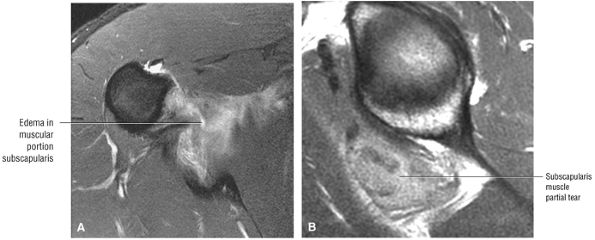

FIGURE 8.102 ● (A) The anterior undersurface of the acromion and the coracoacromial ligament form the coracoacromial arch. The subacromial subdeltoid bursa facilitates the passage of the rotator cuff and proximal humerus under the coracoacromial arch. (B) A superior axial image shows the anterior-to-posterior extent of the coracoacromial (CA) ligament perpendicular to the supraspinatus tendon. The fluid in the subacromial-subdeltoid bursa represents fluid between two serosal surfaces in contact with each other. One serosal surface is contributed by the undersurface of the coracoacromial arch and deltoid, and the other serosal surface is on the bursal side of the cuff.

|

![]() |

FIGURE 8.103 ● Pseudospur. The normal broad attachment of the coracoacromial ligament to the inferior surface of the acromion is shown on (A) T1-weighted coronal oblique and (B) sagittal oblique images. The low-signal-intensity acromial cortex (black arrows) and adjacent coracoacromial ligament and lateral slip of the deltoid attachment (white arrows) give the false impression of a small subacromial spur in the coronal plane. This pseudospur should not be misinterpreted as impingement; otherwise, unnecessary acromioplasties may be performed on patients with a normal coracoacromial ligament attachment and no associated acromial spurs.